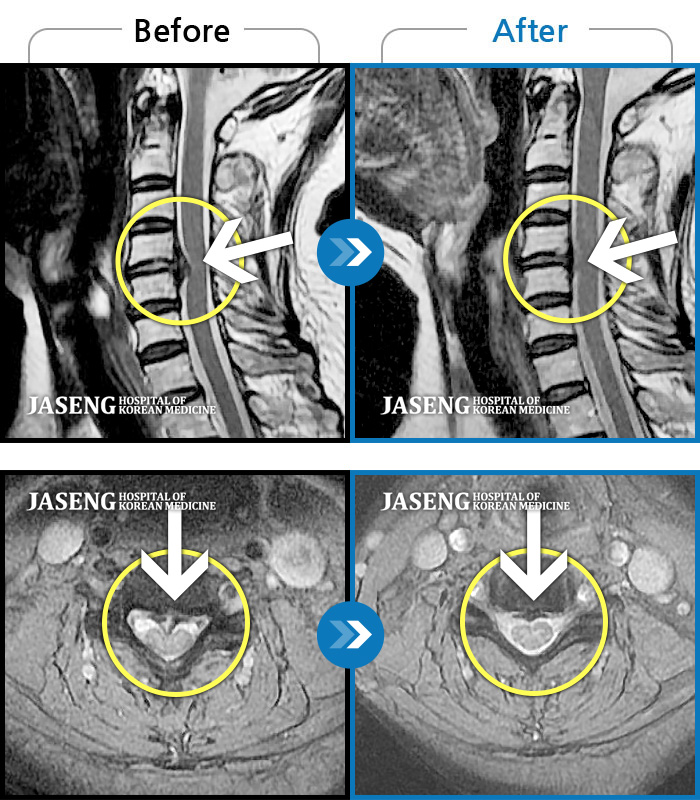

교통사고로 인해 기존의 퇴행성 디스크가 파열되어 극심한 경추의 통증과 손의 힘 빠짐, 손가락의 저림 증상을 호소하였음

2024.04.20 ~ 2024.11.02